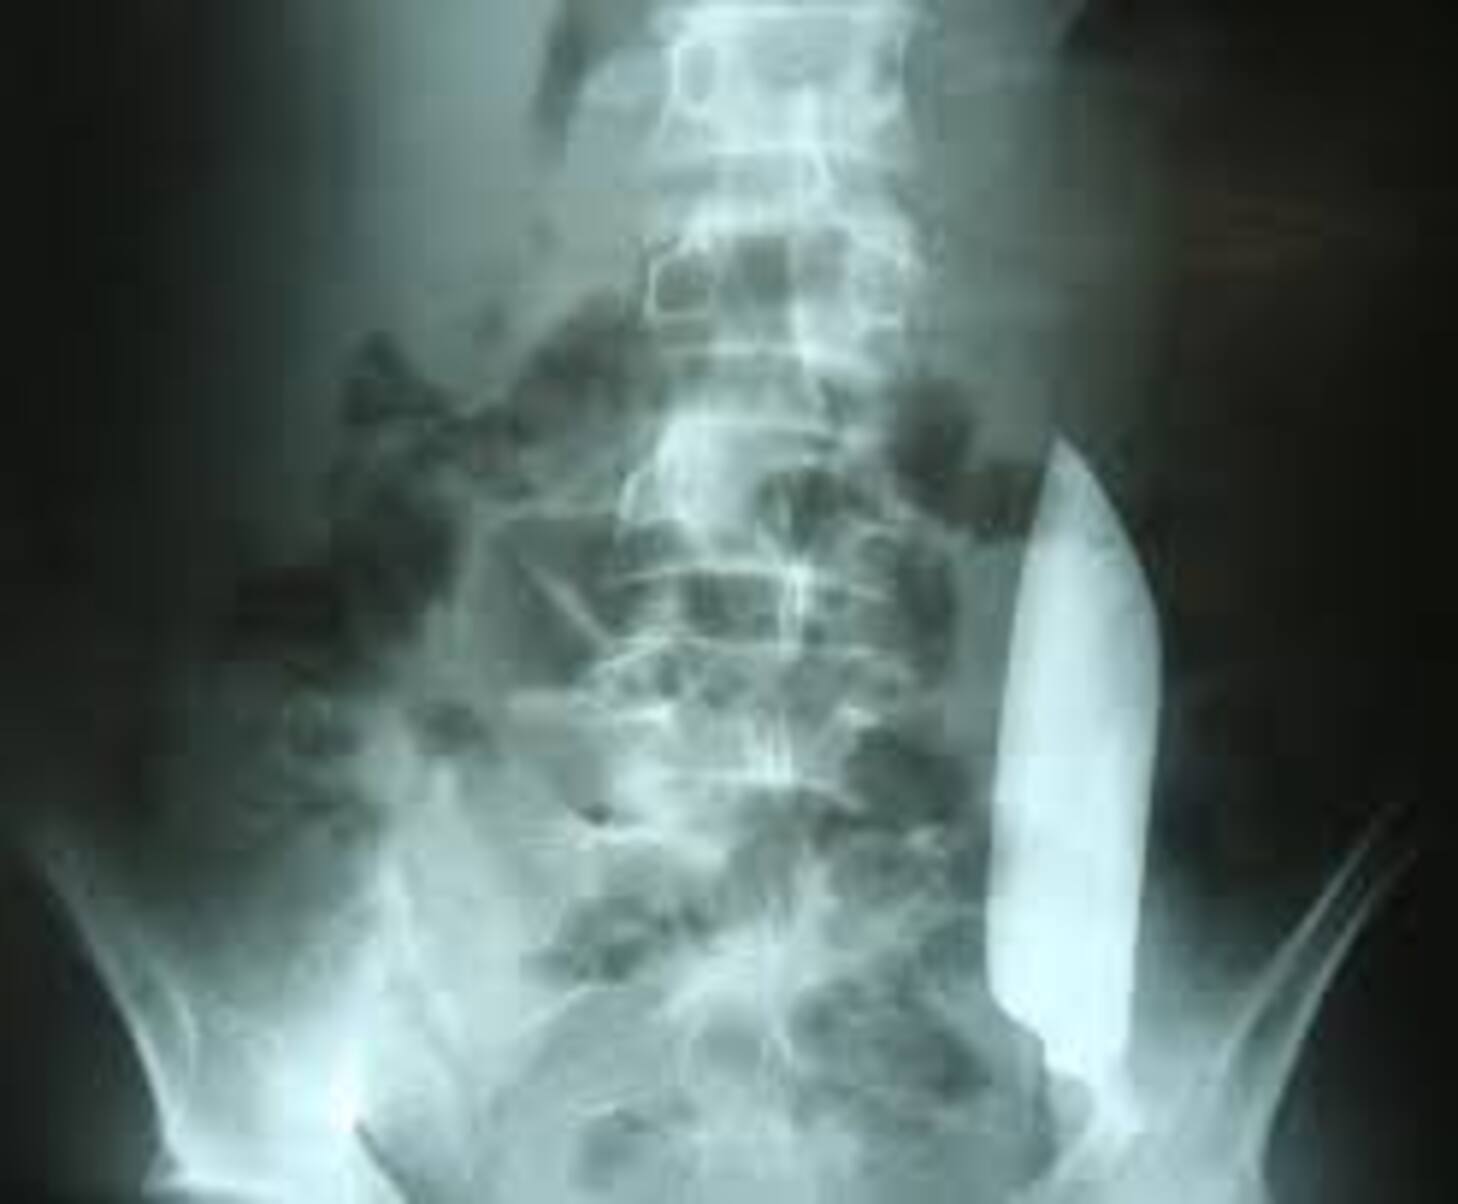

Un patient vit avec une lame de couteau de 15 cm dans le ventr…

C’est une affaire médicale qui défie la logique. Au Népal, un homme poignardé lors d’une bagarre s’est présenté dans une simple pharmacie pour se faire soigner… sans savoir qu’une lame de couteau d…